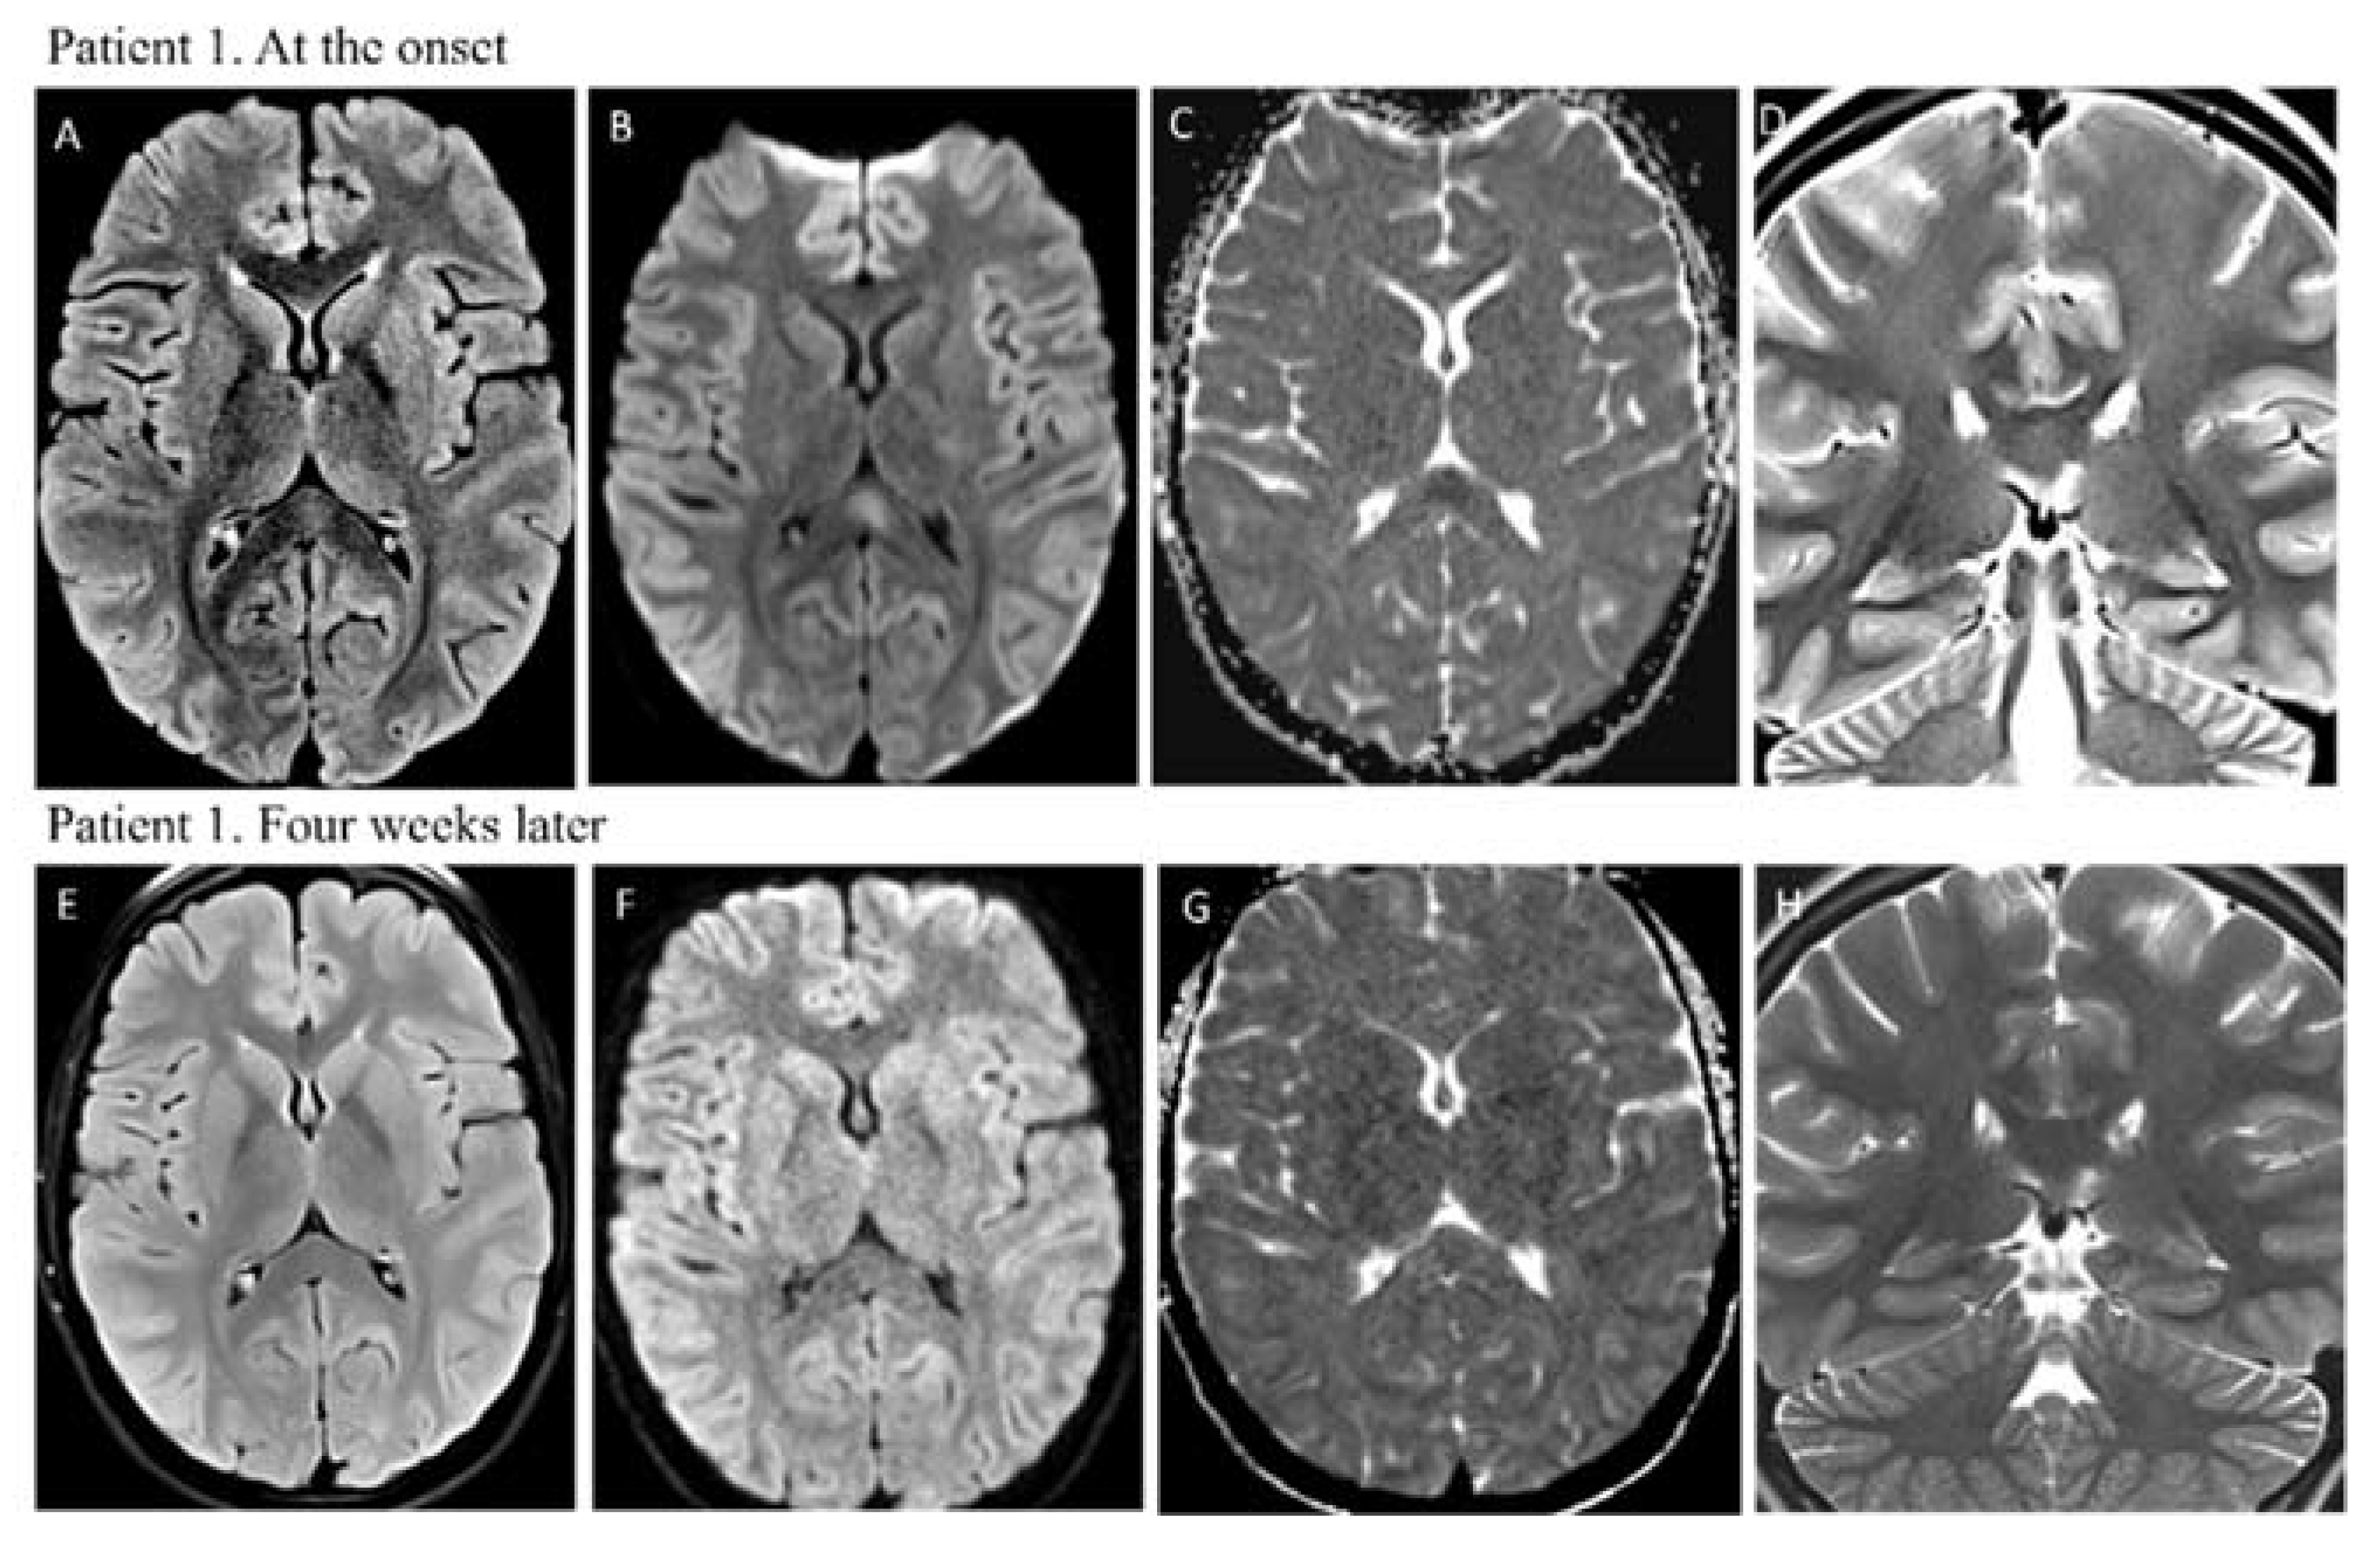

1.1. Case Report 1

| Brain Imaging | MRI: hyperintensity on T2-weighted images in the splenium of the corpus callosum with restricted diffusion | MRI: hyperintensity on T2-weighted images in the splenium of corpus callosum with restricted diffusion |